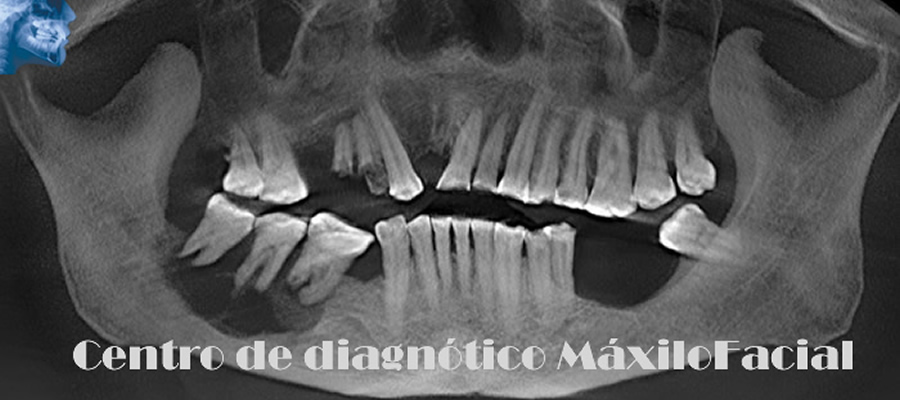

Radiografía Panorámica Dental

Permite obtener una apreciación global de los maxilares, a través de ella podemos detectar caries, enfermedad de las encías, quistes, tumores, fracturas, etc. Muchas de estas patologías son detectadas de forma casual, lo que la convierte en un estudio de protocolo a la hora de iniciar un tratamiento odontológico.

A continuación queremos mostrarle nuestra galería con algunas imágenes de casos llegados a Cedimax - Centro de Diagnóstico Maxilofacial, si requiriera más ejemplos de casos no dude en contactarse con nosotros.